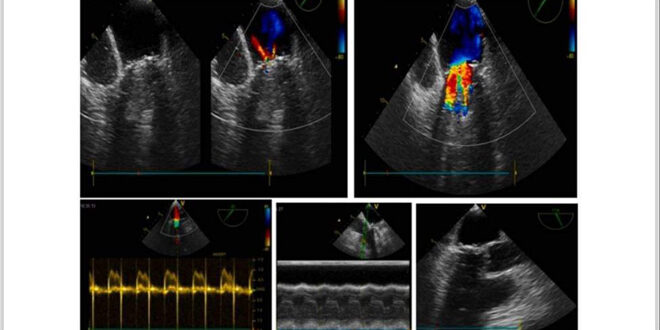

وبعد شهرين من العلاج بين الدكتور سليمان أن المريضة عادت بترقي زلة تنفسية على أقل جهد حيث تبين بالايكو عبر جدار الصدر وجود “أم الدم الكاذبة” على الجدار الحر للبطين الأيسر وتم تأكيد التشخيص بإجراء التصوير بالأشعة المقطعية متعدد المقاطع باستخدام الكمبيوتر إضافة لإجراء قثطرة قلبية لنفي السبب الإكليلي وكانت نتيجة القثطرة شرايين إكليلية طبيعية.

وأشار الدكتور سليمان إلى أن المريضة خضعت لاستئصال جراحي لـ “أم الدم الكاذبة” مع إغلاق فوهة التمزق في البطين الأيسر برقعة مع الخياطة على عدة طبقات وتخرجت المريضة بعدها بحالة عامة جيدة.